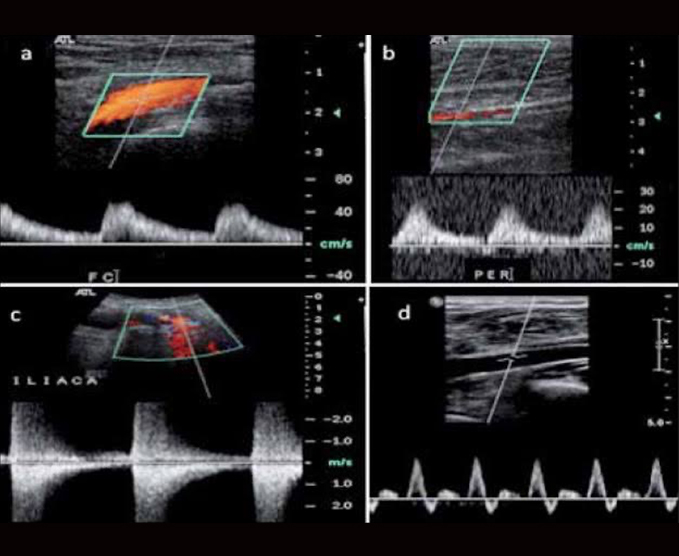

Ecografía Doppler

El Doppler es un tipo especial de ecografía que brinda la posibilidad de ver y estudiar las ondas de velocidad de flujo de ciertas estructuras del cuerpo, como los vasos sanguíneos, por lo que se utiliza para estudiar las arterias, venas y la vascularización de los órganos.

- Doppler arterial

- Doppler venoso